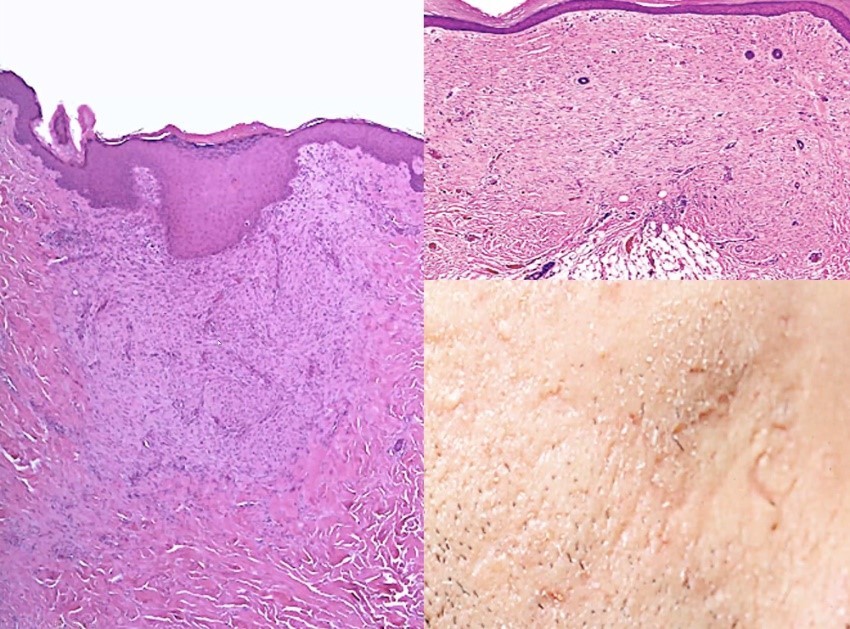

Vad visar bilden?

Ostig nekros

Övre röda pil visar döda nekros, väl avgränsad process (görs för att avgränsa inflammationen)

Många har haft tuberkulos utan att veta det, de har immunsvar som kan avgränsa mykobakterier så att det bildas granulom, dystrofisk förklakning och bindvävsbildning runt om